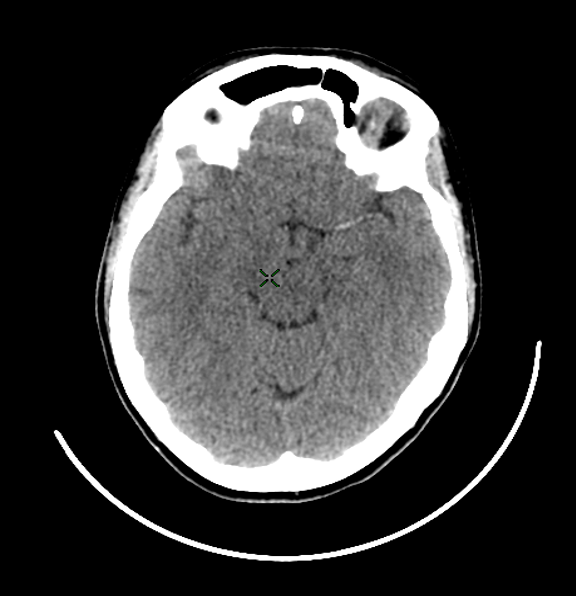

What type of stroke is shown ?

Haemorrhage stroke